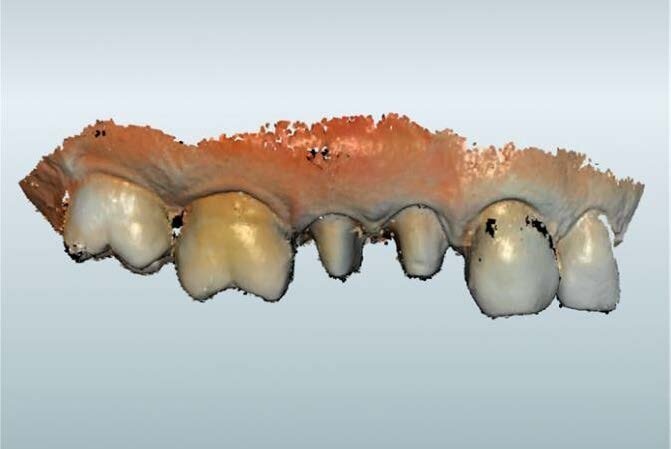

Fig. 2: MyCrown view of the concerned teeth

Later on, HD Spray was applied and the scan with MyCrown Scan camera started. First, we scanned the stumps, then the antagonists, and finally we proceeded with scanning the vestibular area, with the teeth in position for maximum contact.

After correlating the models with the software, we started tracing the margins. Moreover, after the definition of the insertion axes, MyCrown Software gave us its design proposal of the crowns. Obviously, software proposal of the crown design is based on the anatomy of the other teeth of the patient. This does not prevent us from modifying the tooth anatomy based on the neighbor and antagonist teeth.